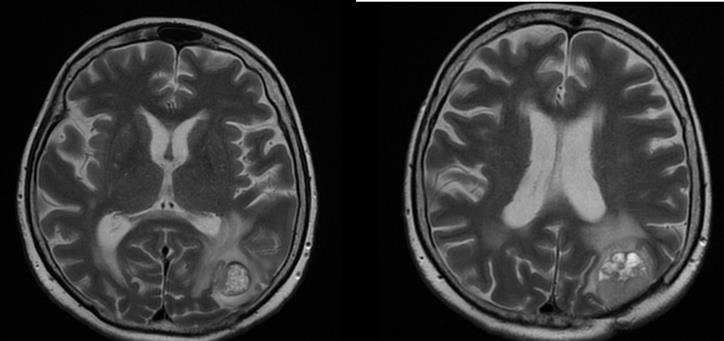

We present a 57-year-old woman with solitary intracranial plasmacytoma (SICP). Intensively modulated prophylactic wholebrain radiotherapy (WBRT) with DD 3 Gy up to TD 30 Gy / Biologically equivalent dose (BED) 38 Gy / 5 times per week was performed. The first local recurrence occured 1.5 years after the WBRT, and the second local recurrence occured 5 months after its surgical extirpation (Figure 5 & 7/A).

Figure 5: MRI - Second local recurrence of solitary intracranial plasmacytoma after prophylactic whole-brain radiotherapy.

From the studies: Bone scintigraphy, bone marrow biopsy, serum protein immunoelectrophoresis, serum levels of immunoglobulins, serum lactate dehydrogenase, calcium, albumin, renal function, beta-2 microglobulin levels - all without abnormalities. We performed local intensity-modulated radiotherapy (IMRT) by the VMAT method in the area of recurrence up to TD 45 Gy with DD 1.8 Gy / 25 fractions (Figure 6).

Figure 6: Local IMRT by the VMAT method in the area of second local recurrence of solitary intracranial plasmacytoma up to TD 45 Gy with DD 1.8 Gy / 25 fractions.

Due to seizure symptoms 2 weeks after RT, the irradiated relapse (Figure 7/B) was operated and histologically confirmed as necrotic brain tissue.

Figure 7: CT of the second local recurrence: A / before the local RT; B / Over 50% reduction of tumor volume after local RT up to TD 45 Gy with DD 1.8 Gy.